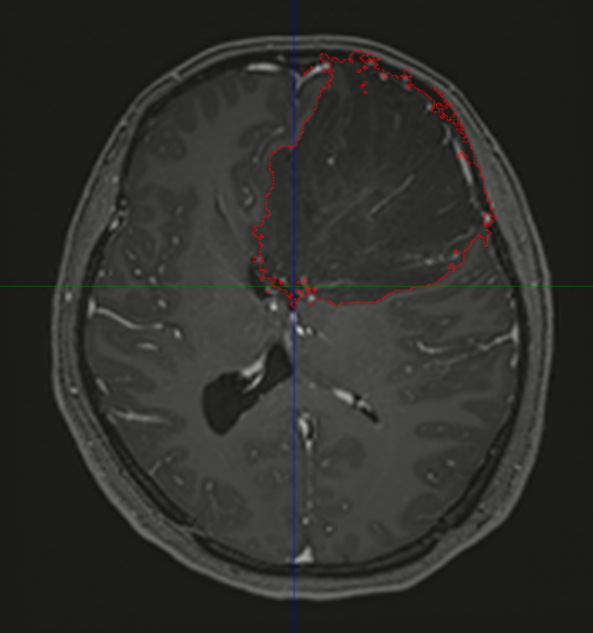

图中所示红色区域为肿瘤

因年前工作繁忙,陈女士出现头部不适,以为是颈椎问题,在附近医院按颈椎病治疗,然而1个月后病情不但没有减轻,反而越来越重。陈女士感觉自己不但头越来越痛,清晨还有明显的恶心感,尤其觉得“脑子不清楚了”,每天生活在朦胧中一样,对饭菜味道感觉也越来越迟钝。意识到情况不对劲的陈女士,赶紧在家人的陪同下到上一级医院进行检查,这不查不知道,一查吓一跳,颅内长了一个直径达10cm的巨大肿瘤!